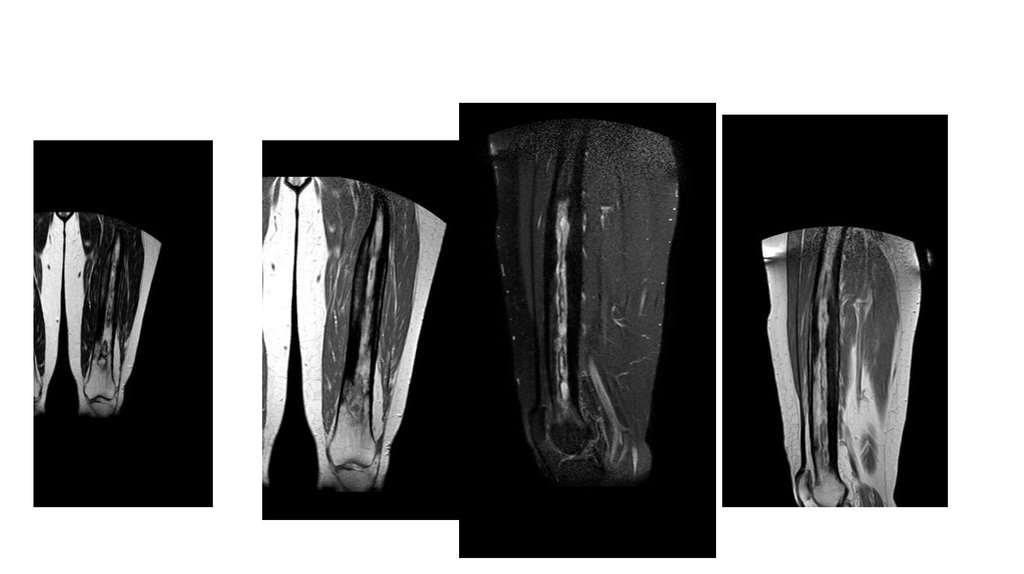

Воспалительные заболевания опорнодвигательного аппарата

«Воспалительные

заболевания опорнодвигательного аппарата»